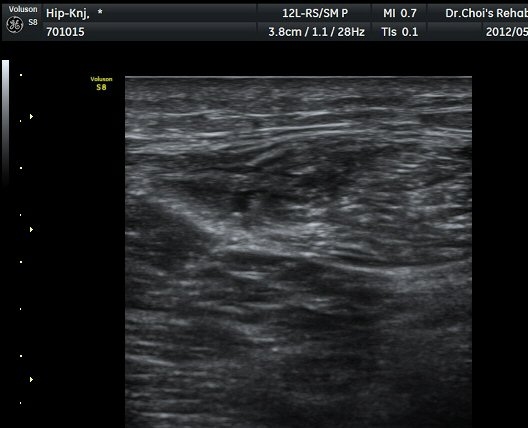

ÀüÇÏÀå°ñ±Ø(AIIS) Ⱦ´Ü¸é °Ë»ç»ó ÀüÇÏÀå°ñ±Ø°ú µÇÅðÁ÷±ÙÀÇ ÈûÁÙÀÌ °üÂûµÈ´Ù(±×¸² 1).

ŽÃËÀÚ¸¦ ¾Æ·¡·Î À̵¿ÇÏ´Ï ´ëÅðÁ÷±Ù³»¿¡ Àú¿¡ÄÚ º¯º¯ÀÌ °üÂûµÈ´Ù(±×¸² 2, 3).